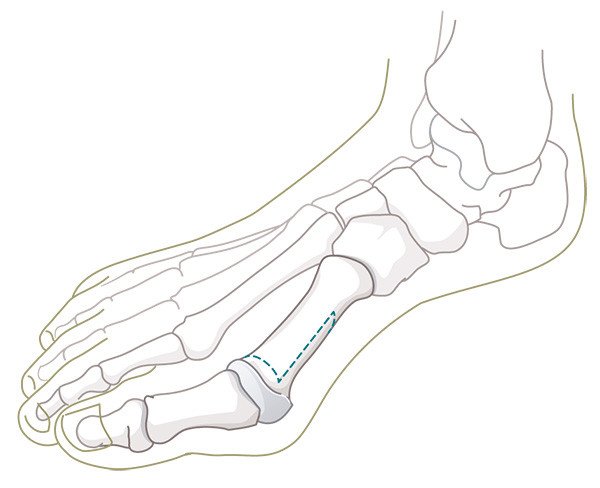

Die Ursachen für die Entstehung einer Hallux-valgus-Deformität sind vielseitig, wobei eine erbliche Veranlagung die Hauptrolle spielt. Die Grosszehe knickt nach aussen ab, der Mittelfussknochen weicht, wie im Bild (Abbildung 1) ersichtlich, zunehmend nach innen, d. h. zur Körpermitte hin, und bildet das augenfällige und schmerzhafte Überbein.

Durch diese Fehlstellung verliert die Grosszehe einen Teil ihrer wichtigen Stützfunktion und der benachbarte zweite Mittelfussknochen (Abbildung 2) wird chronisch überbelastet. Die Überlastung zeigt sich in der häufig beobachteten, schmerzhaften Hornhautverdickung unterhalb des zweiten (oft auch dritten) Mittelfussköpfchens. Die dort stark strapazierten Bänder und die Gelenkkapsel der zweiten (und dritten) Zehe können einreissen, sodass die Zehe keinen Halt mehr hat und sich eine Hammerzehe bildet (Abbildung 3).